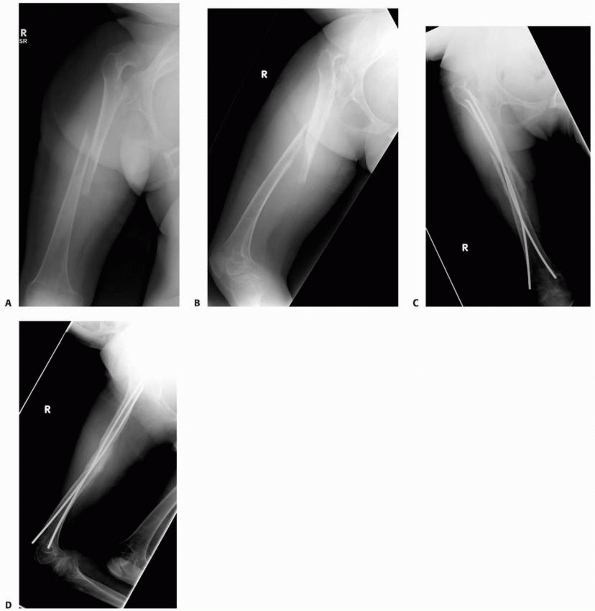

FIGURE 6-19

An 8-year-old girl sustained a pathologic fracture of the femur after falling off her bicycle. She denied symptoms previous to this injury. The radiographs (A,B) showed a grossly displaced fracture through a poorly defined, mixed lesion in the midshaft of the femur (arrow); there is disorganized periosteal reaction with sunburst sign. T2-weighted coronal (C), sagittal (D), and axial (E) MRI showed extensive soft tissue mass; the neurovascular bundle does not seem do be involved by the tumor mass. The patient underwent biopsy that confirmed osteogenic sarcoma and fracture stabilization with an external fixator at a referring institute. Note that the external fixator pins were inappropriately placed too far from the tumor and fracture site (F), increasing the contaminated area. The surgical treatment options were limited to rotationplasty and amputation. (Figures reproduced with permission from The Childrens Orthopaedic Center, Los Angeles, CA.) |